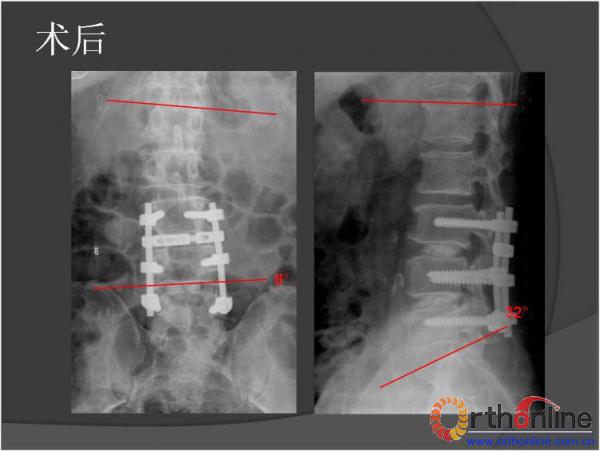

北京军区总医院骨科李放教授报告了一例腰椎管狭窄脊柱融合术后、退变侧凸加重并出现邻近节段退变病、而后进行翻修的病例。患者男性,64岁,2009年因腰椎管狭窄症行椎板减压,L3-4、L4-5PLIF手术,术后3年间疗效满意,后由轻度扭伤后再度出现腰痛及下肢疼痛,经检查后发现L2-3间盘退变、L1-2间盘突出并出现退变性腰椎侧凸,于2013年2月行翻修手术后痊愈。